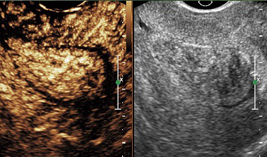

二维超声:观察子宫及双侧卵巢形态和结构变化,对子宫、输卵管、卵巢及盆腔的疾病做基础性排查。